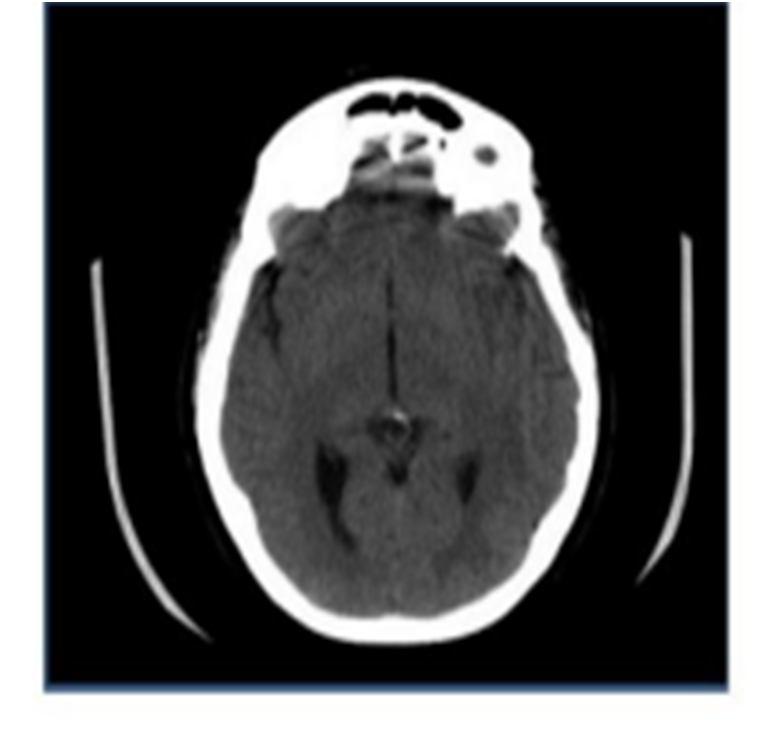

Figure 1 shows the key phases of the general pixel-level image fusion approaches. They are as follows: 1) A mathematical transform is performed to the input images to obtain the transform coefficients 2) The fusion process is employed to create the fused coefficients, and 3) an inverse transform is performed to the fused coefficients to create the final fused image. Imaging techniques such as Computed Tomography (CT) and Magnetic Resonance Imaging (MRI) in the field of medical imaging have supplied doctors with information on the structural characteristics, soft tissue, and so on of the human body. Distinct imaging technologies retain different properties, and different sensors receive different imaging information from the same component. Traditional medical image fusion methods are classified into two categories: spatial domain and transform domain. Discrete Wavelet Transform was used to merge multimodal medical pictures such as computed tomography (CT) and magnetic resonance imaging (MRI). The advantages of transparent bone are combined by combining MRI and CT. To compensate for the absence of data in a single imaging, information in CT pictures and clear soft tissue in MRI images are used. A guided filtering-based MRI and CT fusion technique (GF) is suggested. The fused picture not just preserves the edge information of the source image but also extracts feature information, resolving the edge degree and clarity issues. The visual inspection of fusion findings shows that brightness and correlation have improved noticeably. The discrete wavelet transform may generate diverse input frequency signals while keeping stable output appropriate location in the temporal and frequency domains, which aids in the preservation of picture particular information. The wavelet transform overcomes the restrictions of principal component analysis and provides an effective visual and numerical fusion effect. The source picture is improved and preprocessed, and the intensity component of the CT image is extracted using the IHS transform, which maintains more biological information and decreases color distortion. To get high- and low-frequency subbands, the DWT transform is applied to the intensity components of MRI and CT. The high and low- frequency subbands are fused using distinct fusion criteria, and the fused picture is obtained using the inverse DWT transform. Figure shows a block schematic of a 1-step 2-D DWT. To fuse the decomposing high-frequency coefficients, the absolute high-value approach is utilized, the weighted average method is employed, the predator-optimizer is used to calculate and optimize the weights, and lastly, the inverted transform is used to generate the fused pictures. Fusion is accomplished by the application of two fusion rules. Because high and low frequency coefficients have various meanings, they were fused using different rules. The first set of principles is that bigger wavelet coefficients indicate important picture characteristics such as corners and edges, hence larger wavelet coefficients are preferred. The wavelet factor is the most often used method for fusing features since larger values indicate stronger edges and are considered as a significant component of relevant information. Low wavelet coefficient values represent source image approximation, hence averaging is employed to obtain information about both source pictures. An Inverse Discrete Wavelet Transform is used to get the fused picture after approximating the derived wavelet coefficients. The CT image of a patient brain diseased by Sarcoma is shown in figure 2 and the MRI image of the same patient is shown in figure 3. These two multimodal images were fused by applying the Discrete Wavelet Transform algorithm. After the extraction of the wavelet coefficients and further fusion rule is applied to fuse the coefficients.